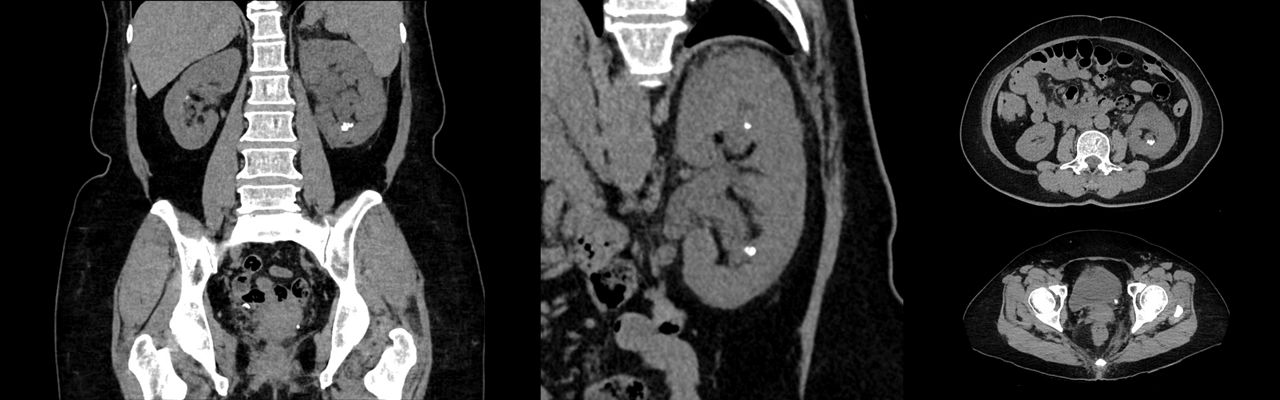

Discovery MI Gen 2

Eine neue Generation der weltweit ersten digitalen PET/CT-Plattform.

Mit der bahnbrechenden digitalen PET-Technologie, der neuesten diagnostischen CT und der fortschrittlichen quantitativen Software wurde Discovery™ MI entwickelt, um Ihre Forschung zu beschleunigen und Ihre klinische Arbeit zu verbessern. Der Discovery MI Gen 2 ist die nächste Generation dieser unglaublichen Bildgebungstechnologie. Das System wurde so konzipiert, dass es eine beeindruckende Abdeckung von 30 Zentimetern erreicht und mit einem diagnostischen CT kombiniert ist, das eine Deep-Learning-basierte Bildrekonstruktion ermöglicht. Die durchdachte Entwicklung ermöglicht zudem effizientere Abläufe für den MTRA. Willkommen bei einer neuen Generation digitaler PET/CT.